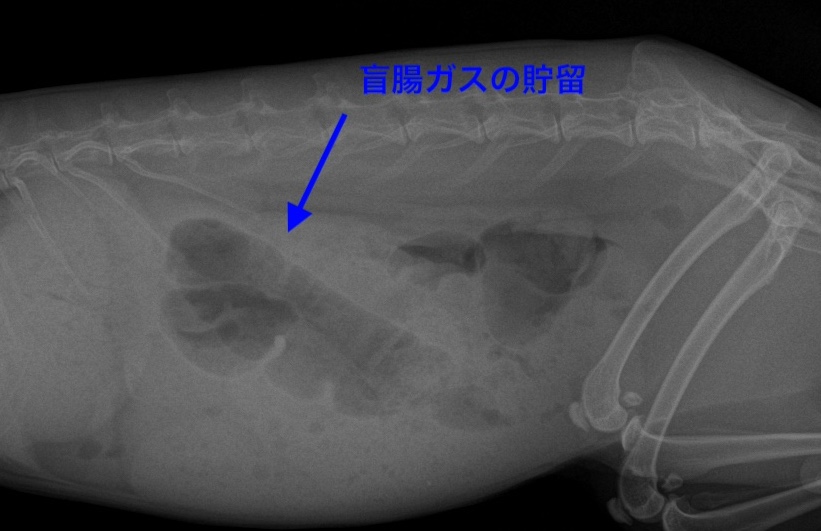

上記にも記載した通り、うさぎの盲腸は大きく、ガスが溜まるとレントゲンにて確認しやすくなります。

*レントゲンにて黒く見える部分が、盲腸のガスになります。